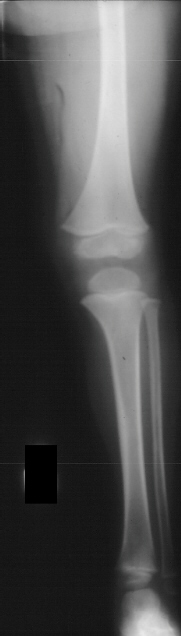

XRAY EVALUATION:

Radiographic examination of the left knee revealed no osseous abnormalities . A fullness of the soft tissues was evident over the fibular head. MRI examination of the left knee displayed a 2 cm. by 0.8 cm. lobulated mass in the region of the common peroneal nerve with no enhancement . On the T-2 weighted sequences there was abnormal increased signal of the tibialis anterior, extensor digitorum longus and peroneus longus muscle bellies suggesting atrophy . EMG/NCS were performed which clearly documented electrodiagnostic evidence of a severe peroneal neuropathy distal to the take-off of the nerve to the short head of the biceps.